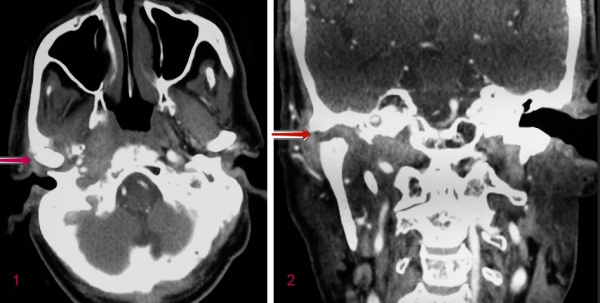

КТ больного со злокачественным наружным отитом. Эрозия височно-нижнечелюстного сустава и непрозрачность мягких тканей барабанной полости. 1 - аксиальная, 2 – корональная